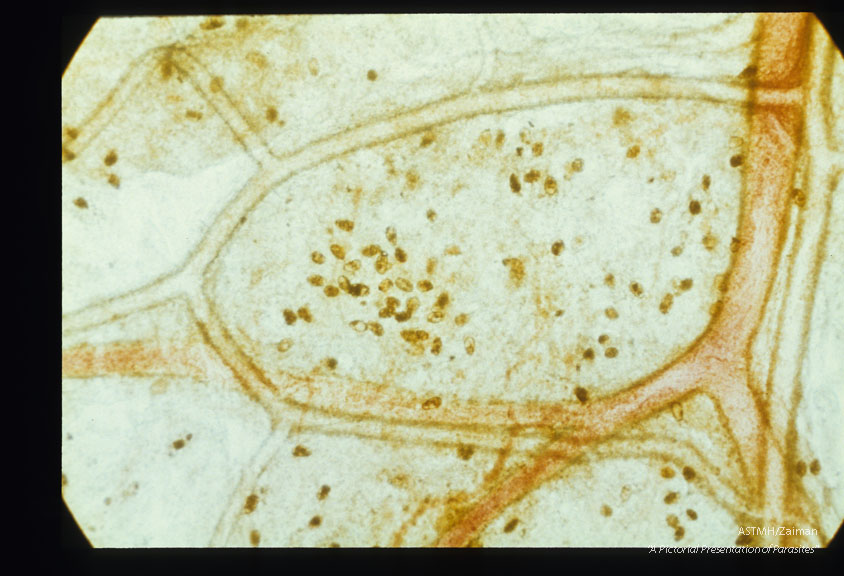

Paragonimus eggs are present in the mediastinum.

Description: Paragonimus eggs are present in the mediastinum.